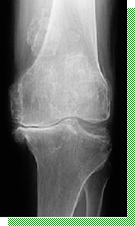

頚の痛み・・・・・・・・・・・・・・・・頚部筋筋膜症(寝たがい、肩こり) 頚の痛み・・・・・・・・・・・・・・・・変形性頸椎症 腰の痛み・・・・・・・・・・・・・・・・変形性脊椎症 腰から足にかけての痛み・・・腰椎椎間板ヘルニア 腰から足にかけての痛み・・・脊柱管狭窄症 肩の痛み・・・・・・・・・・・・・・・・肩関節周囲炎(いわゆる五十肩) 肘の痛み・・・・・・・・・・・・・・・・上腕骨外顆炎(いわゆるテニス肘) 手のしびれ・・・・・・・・・・・・・・ 肘部管症候群 手のしびれ・・・・・・・・・・・・・・ 手根管症候群 手の痛み・・・・・・・・・・・・・・・・ 腱鞘炎(弾発指またはばね指) 手の変形・・・・・・・・・・・・・・・・・ヘベルデン(ヘバーデン)結節 手、足のしこり・・・・・・・・・・・・・ガングリオン 関節の痛み・・・・・・・・・・・・・・・慢性関節リウマチ 膝の痛み・・・・・・・・・・・・・・・・・変形性膝関節症 膝の痛み・・・・・・・・・・・・・・・・・半月板損傷 膝の痛み・・・・・・・・・・・・・・・・・膝前十字靭帯損傷 足の変形・・・・・・・・・・・・・・・・・外反母趾 |

変形性膝関節症 |